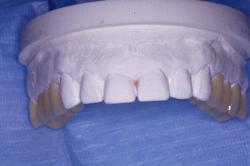

Dents provisoires réalisées au laboratoire

Les 8 dents provisoires sont mises en place.

Noter la béance antérieure qui résulte de la mise en place des dents provisoires sur les secteurs postérieurs